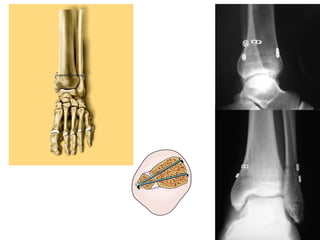

Tibialis Posterior   Sehne